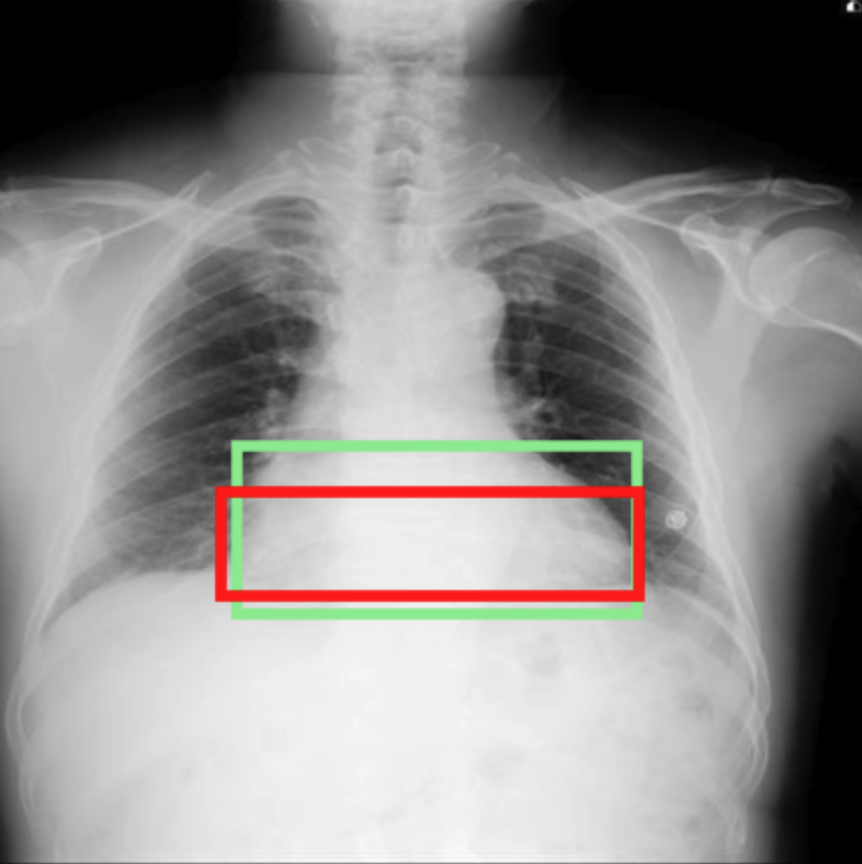

For this task, the instructions are designed such that the user asks the assistant to generate a report for a given CXR, and the assistant responds with the filtered findings corresponding to that CXR (Figure 1a).

a. Report generation

b. Abnormality classification

c. Visual grounding: Anatomy/Abnormality

d. Visual grounding: Phrase

Detecting the location of specific anatomical regions or pathologies on a CXR is an important task for AI assistants. In addition to providing a textual description of the image, they should be able to spot where specific observations are located. This is usually done by predicting bounding box coordinates of top-left and bottom-right corners . While classical object detectors (Ren et al.,, 2016; Redmon,, 2016) tackle this task by leveraging specialized architectures and learning rules, we embark on it with the other text-based tasks via next-token prediction (Equation 1), formatting coordinates into text, enclosed between square brackets. As input images are pre-processed to a unique size by the vision encoder, we normalize these coordinates to the original dimension to obtain floating values between 0 and 1, similarly as in You et al., (2023); Park et al., (2024); Zhang et al., 2024a .

Chest Imagenome (Wu et al.,, 2021), derived from MIMIC-CXR, provides additional annotations to frontal X-ray images, in particular, bounding box coordinates for 29 anatomical regions. In our training data, we randomly select one region per image for each datapoint and create an instruction for anatomical region grounding following Figure 1.

VinDr-CXR (Nguyen et al.,, 2022) contains 18,000 frontal images, each manually annotated by three different radiologists. To merge their annotations, we pre-processed them by fusing bounding boxes of the same pathology using weighted box fusion (Solovyev et al.,, 2021), similarly as in Müller et al., (2024). From this dataset, we design two types of tasks: i) abnormality grounding, asking for the location of a specific abnormality (also following Figure 1c) and ii) abnormality detection, asking the location of all abnormalities, if any (Table 1).

MS-CXR (Boecking et al.,, 2022) provides image-sentence pairs of bounding boxes and corresponding phrases, complementing MIMIC-CXR.

PadChest-GR (Castro et al.,, 2024) also contains grounded sentences derived from the PadChest dataset (Bustos et al.,, 2020).

From the last two datasets, we construct the ‘phrase grounding’ task, where a user asks about the location of a specific sentence from a radiology report, and the assistant provides its associated bounding box coordinates (Figure 1d).